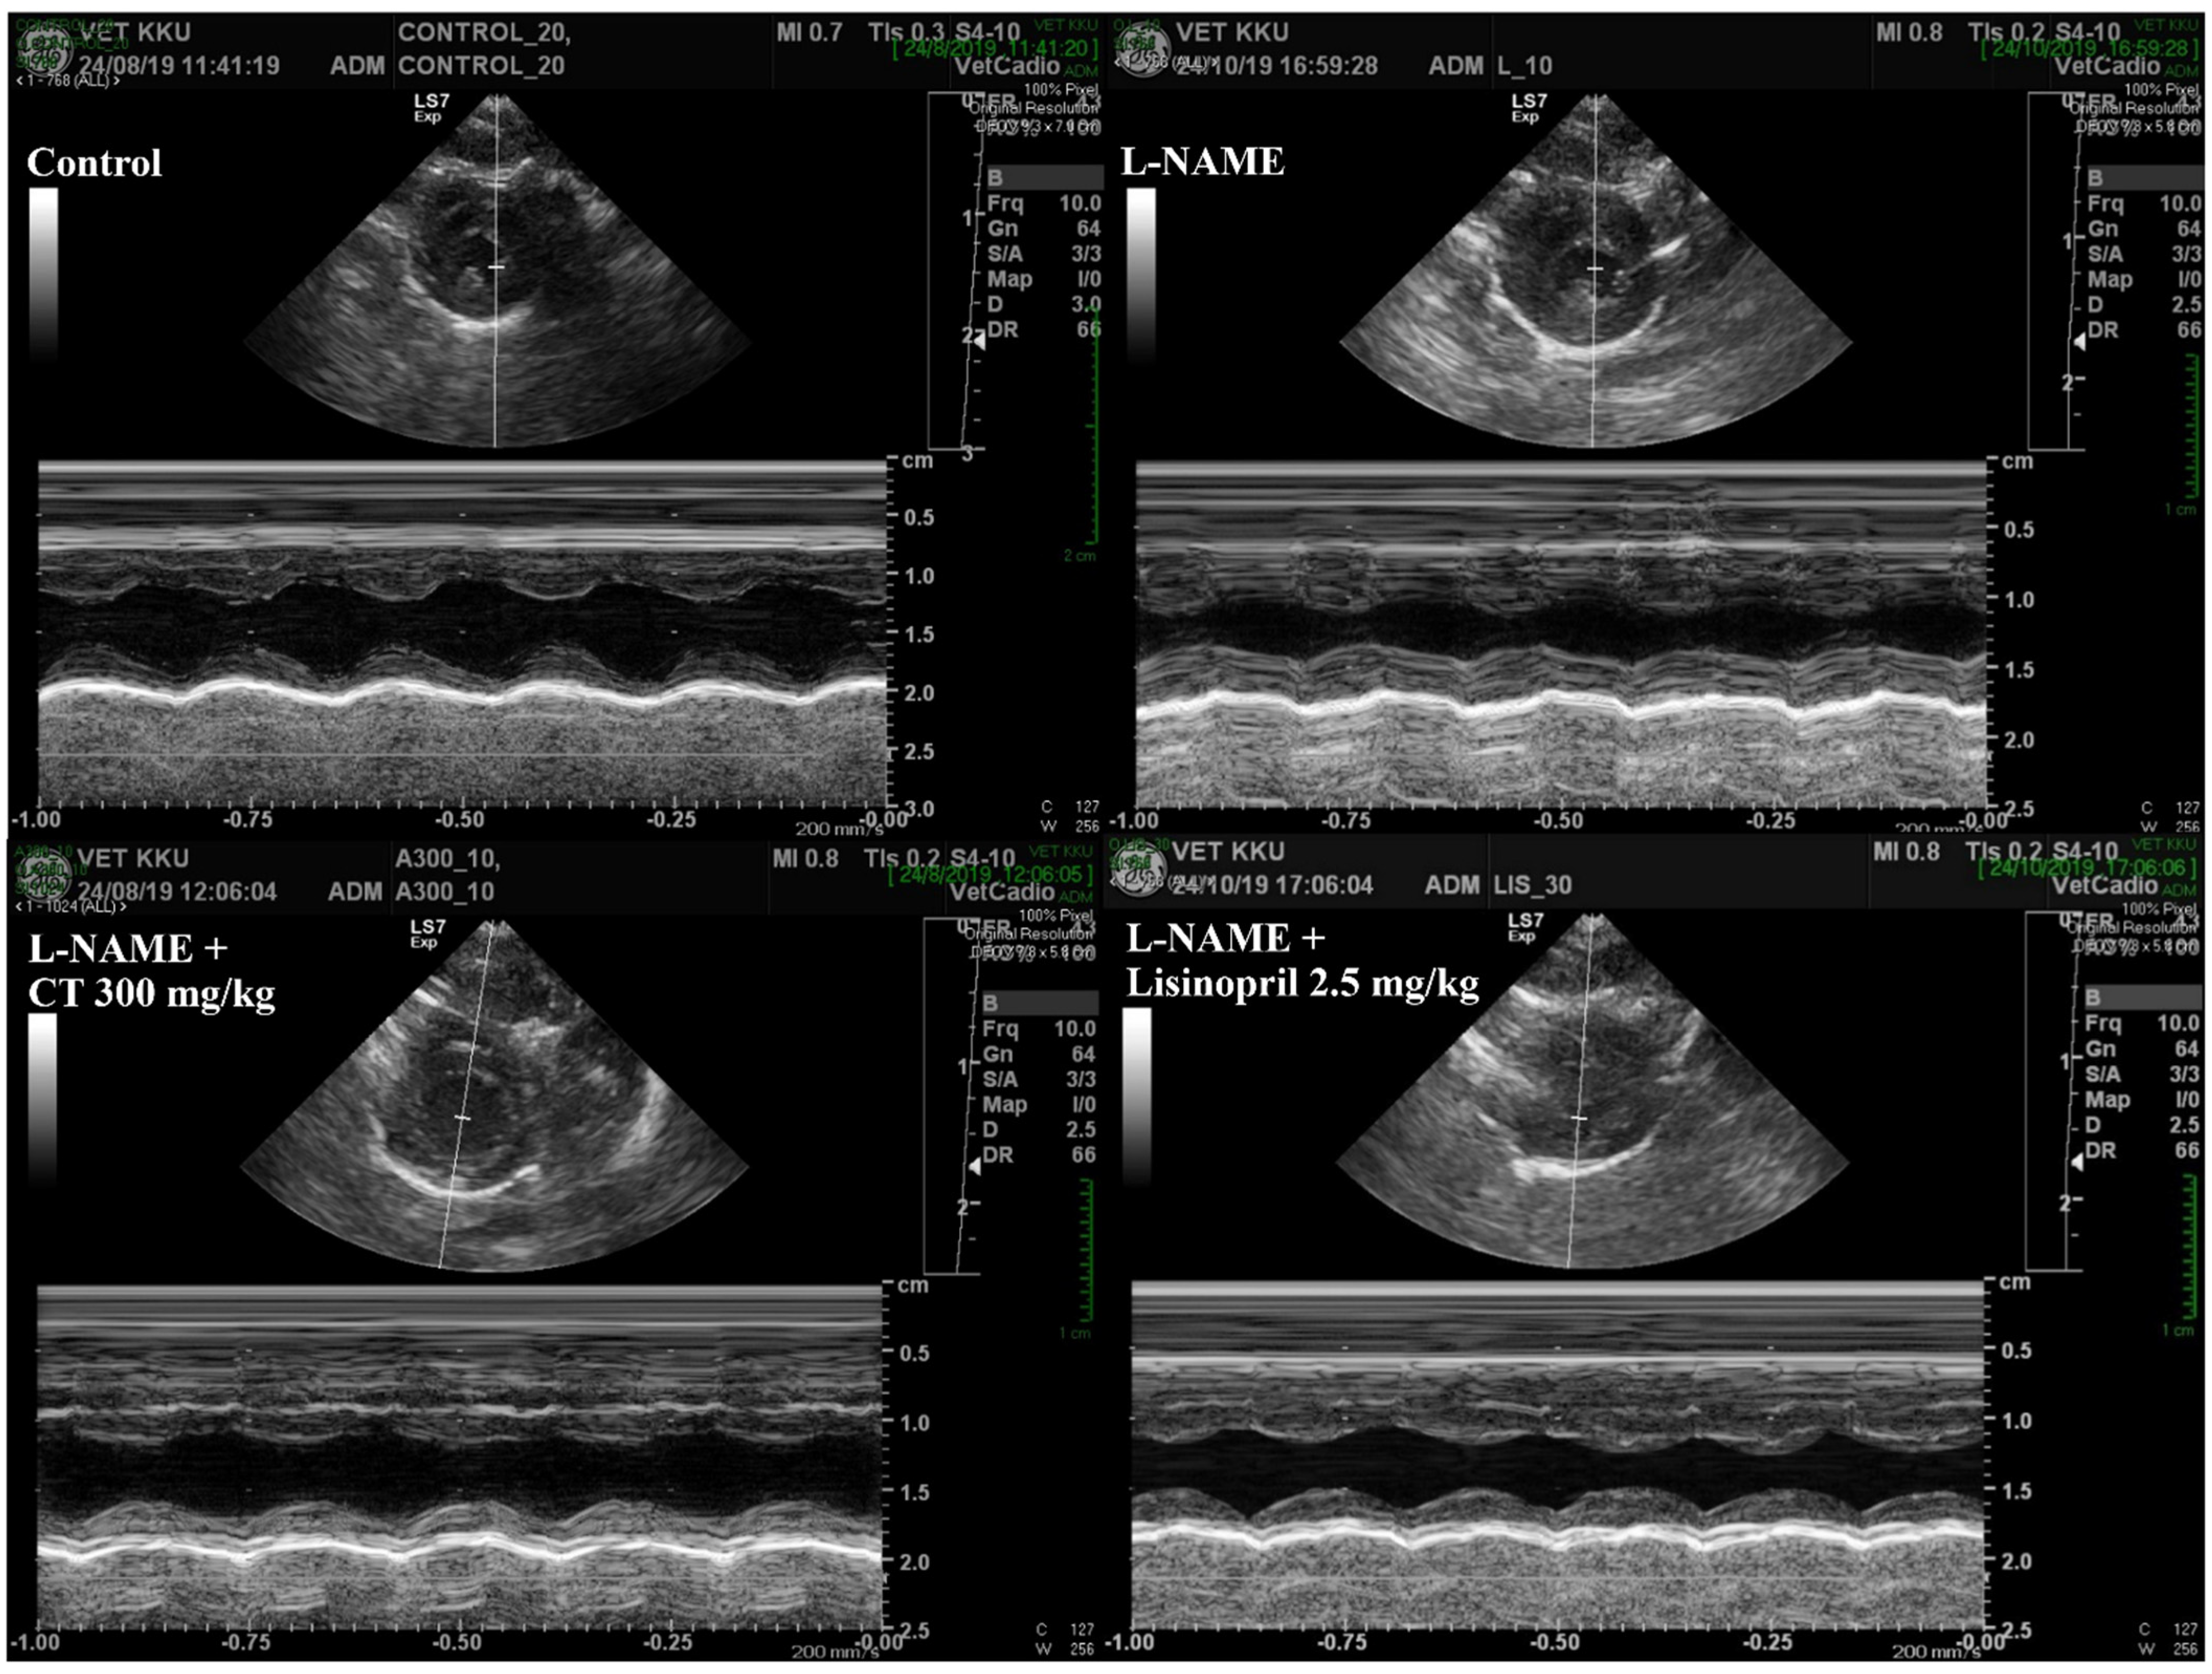

3.5. CT Extract Prevented Cardiac Dysfunction Induced by L-NAME in Rats

An impairment of LV function was observed in L-NAME hypertensive rats, which was characterized by increases in IVSd and LVPWd and decreases in LVIDd, EDV, %EF, SV, and %FS compared with those of control rats (p < 0.05, Table 3). L-NAME rats treated with CT extract showed an improvement in LV function, supported by restorations of IVSd, %EF, SV, %FS, IVSd, and LVPWd compared with untreated rats (p < 0.05, Figure 4). In addition, lisinopril significantly reduced IVSd and LVPWd, accompanied with significant improvements in %EF, SV, and %FS compared with untreated L-NAME rats (p < 0.05; Table 3).

Table 3.

Effects of CT extract and lisinopril on ventricular dysfunction in all groups of the experiment.

Figure 4.

Representative tracings of transthoracic echocardiographs in all groups of rats. CT: Clitoria ternatea Linn. extract.

LV dysfunction and hypertrophy were found in rats under long-term exposure to high blood pressure induced by L-NAME. The LV hypertrophy was supported by increased LVW/BW ratio, LVIDd, and LVPWd, while LV dysfunction was characterized by decreasing SV, %EF, and %FS. The impairment of LV contraction in L-NAME rats in the present study was consistent with the results of a previous study that rats receiving L-NAME had cardiac morphology and dysfunction, as evidenced by increases in IVSd, IVSs, and LVWd, as well as decreases in LVIDd, EDV, %EF, SV, and %FS [5]. These cardiac disruptions induced by L-NAME were alleviated in rats treated with CT extract. This might suggest that the cardioprotective effects of CT extract in the present study are likely relevant to its beneficial effects on blood pressure, vascular function, oxidative stress, and RAS activation. Additionally, the molecular mechanisms involved in the effect of CT extract on cardiac abnormalities were revealed, as associated with inflammation through the Ang II/AT1R/NOX2/NF-κB pathway. We found that the elevated NF-κB expression and TNF-α in the cardiac tissue of hypertensive rats were suppressed in CT extract-treated rats. Several studies have described that the activation of the NF-κB signaling pathway is required for the hypertrophic growth of cardiomyocytes [22,55]. Ang II-induced ROS production leading to the activation of NF-κB and inflammation has been well-described [16]. Furthermore, the preventive effects of CT extract on lipopolysaccharide-induced inflammation in macrophage cells have been shown [56].